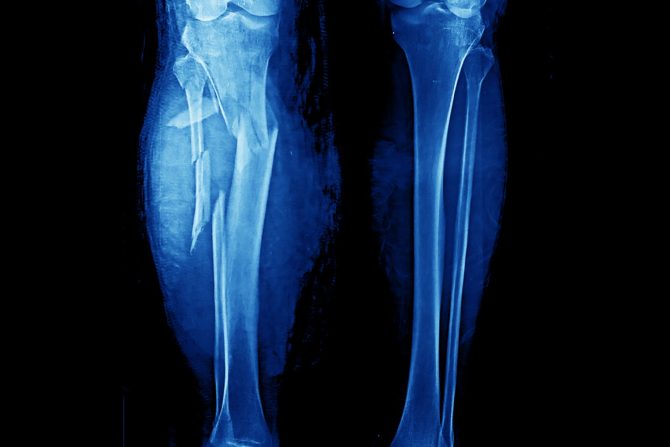

Male frakture mogu biti bolne i traumatične, ali one koje nastanu kao posledica saobraćajnih nezgoda, pada sa velike visine ili čak i bez ekstremnih uslova za povrede su potpuno drugačijeg nivoa ozbiljnosti. Takvi incidenti mogu izazvati teške povrede celog tela, sa višestrukim lomovima kostiju, često i na više mesta.

Prema rečima dr Natali Kejsmir (Nathaly Casemerr), vanrednog profesora ortopedije i rehabilitacije na Yale Medicine, frakture se nazivaju „kompleksnim” kada se kost prelomi na više mesta odnosno komada, kada je meko tkivo oko kosti ozbiljno oštećeno ili kada pacijent ima druga oboljenja ili povrede koje otežavaju lečenje i oporavak.

Prema njenim rečima, u dijagnostici se koriste klinički pregled, laboratorijske analize i radiološke metode, uključujući rendgen i kompjuterizovanu tomografiju (CT).